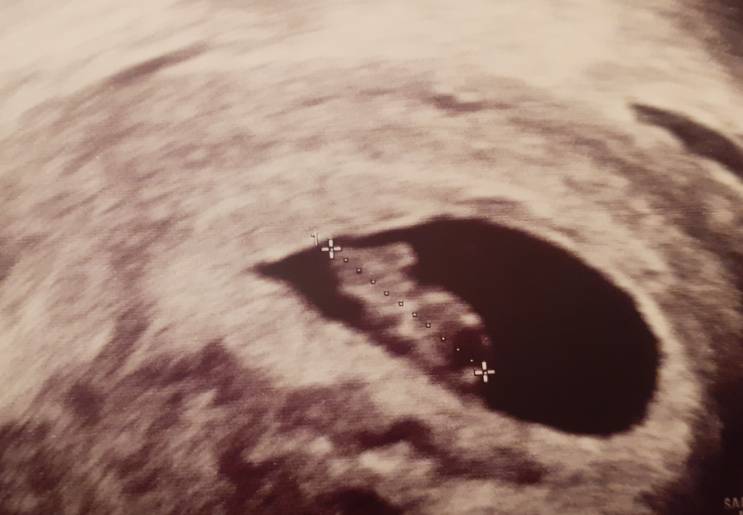

Hej, ja z tego wszystkiego przyspieszylam wizytę i byłam dziś.

Fasolka ma się dobrze i słyszałam serduszko (bije ok 160 ud.)

Wszystko byłoby super, gdyby nie ten wirus, miałam pracować dalej a tu dr doradza żeby siedzieć w domu już do końca ciazy:/Zobacz załącznik 1093037

Gratulacje. Ale już fajnie kształt widać. Mały człowieczek [emoji7]